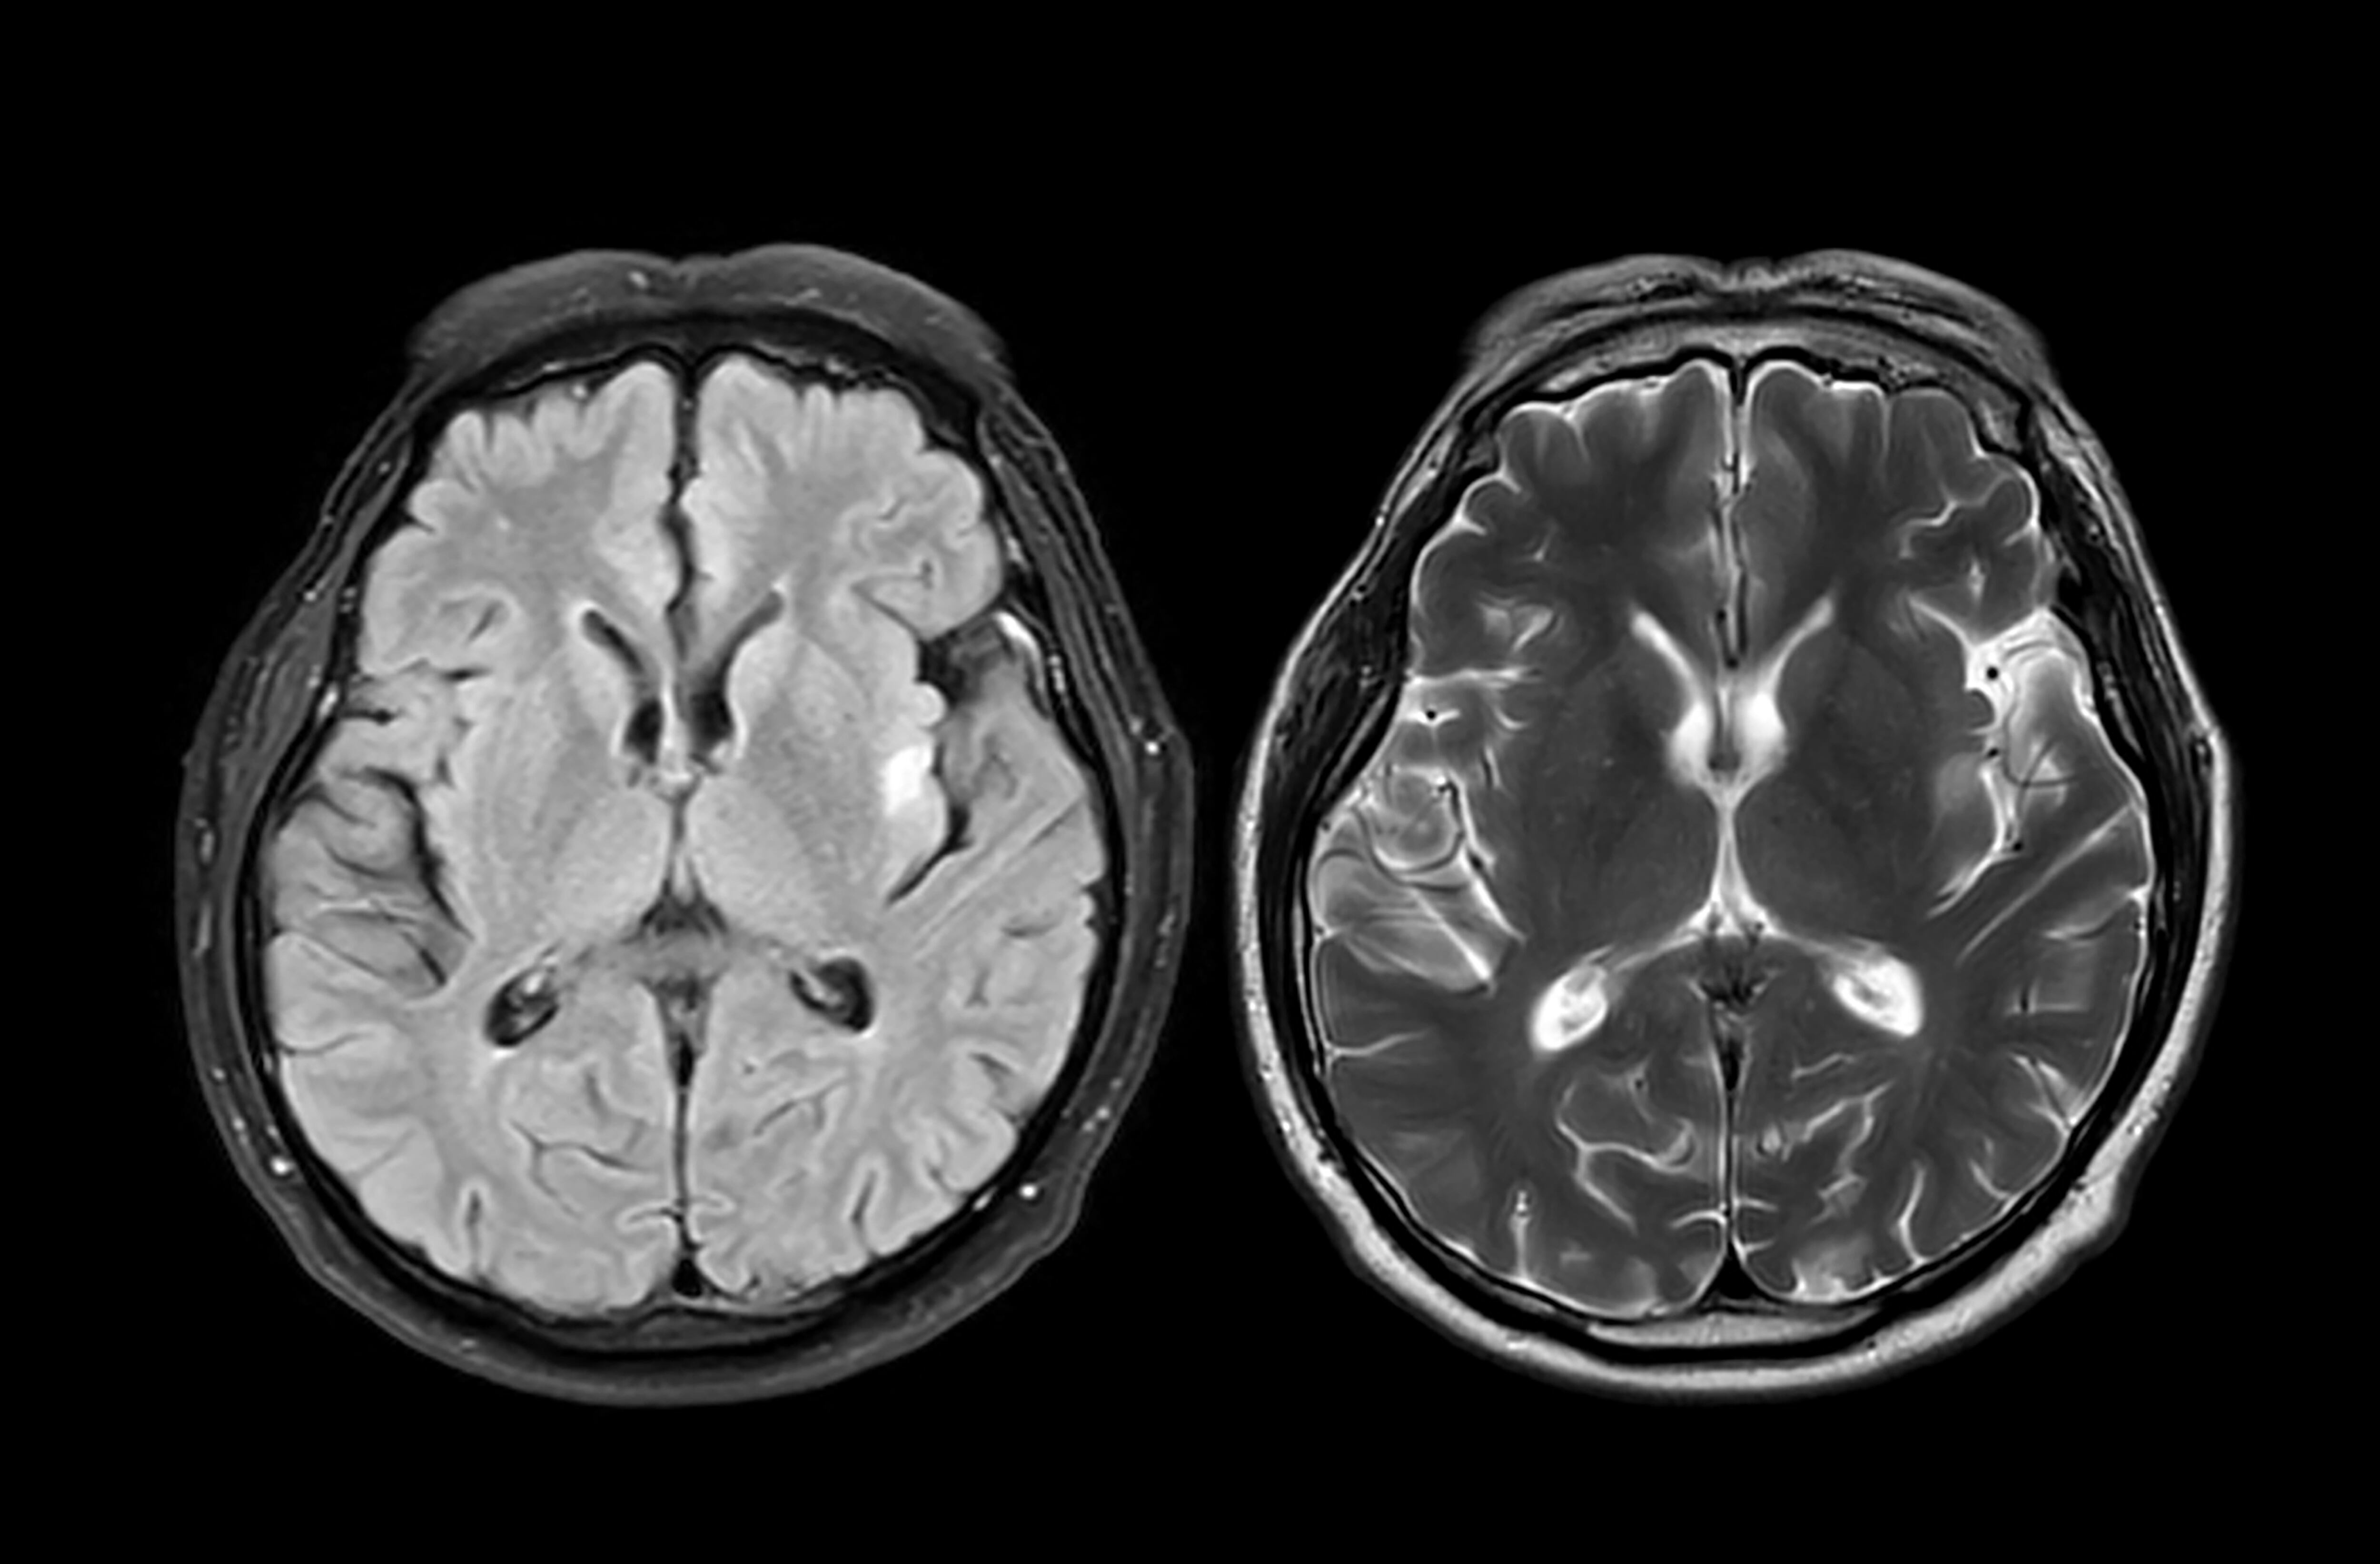

Descifran el mapa de proteínas que podría revolucionar la detección del párkinson y el alzhéimer. / mr.suphachai praserdumrongchai